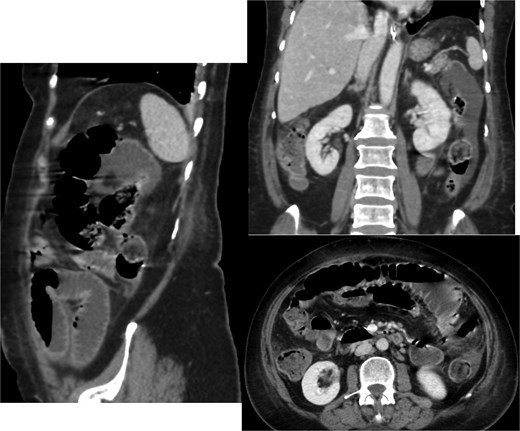

Given the absence of a stone in the ileum, we continued with conservative management. A repeat CT scan was performed 2 days later (Fig. 2). The new imaging demonstrated that the gallstone had passed through the ileum and had reached the mid descending colon. As the stone had migrated to the colon, and the CT showing picture of paralytic ileus, the decision was made to continue with conservative management, including monitoring the patient’s symptoms and providing supportive care.

Interval passage of the previously small bowel obstructing gallstone seen now at the mid descending colon with proximal colonic distention however no signs of mechanical bowel obstruction. The small bowel loop is dilated and fluid-filled without definite transition zone; there is associated mild small bowel thickening, findings are likely representing postoperative changes.